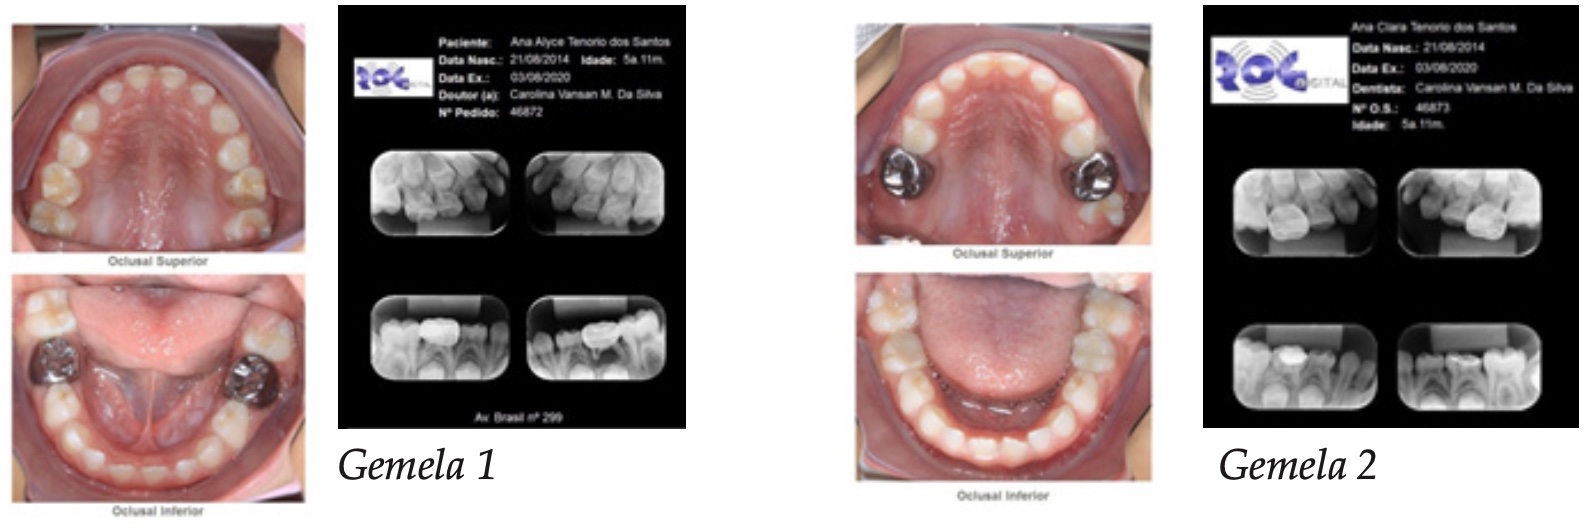

En tal sentido, la gemela 1 recibió restauraciones en los dientes 75 y 85 en resina compuesta, pues como supradicho, ya había recibido restauraciones invasivas (Figura 3). La gemela 2 recibió restauraciones ionómero en los dientes 55 y 56 a través de la filosofía de ART (Tratamiento Restaurador Atraumático). También, en el diente 75, pulpectomía y corona de acero debido la gran destrucción coronal, procedimiento que proporciona mejor preservación del tratamiento endodóntico (Figura 4). Los criterios usados para la elección del tratamiento de las niñas están basados en evidencias clínicas y científicas de la mínima intervención del tratamiento de HMD.

Figura 4: Gemela 2: Imágen clínica y radiológica sacadas al final del tratamiento. Se nota: en la imagen 1, fotografía de la sonrisa; en la 2 (dos), radiografías periapicales; en las imágenes 3 y 4 se ve imágenes intra bucales de las caras oclusales de las arcadas inferiores y superiores. Se observa que los dientes 55 y 56 tratados con coronas de acero y los dientes 75 y 85 restaurados con resina compuesta.